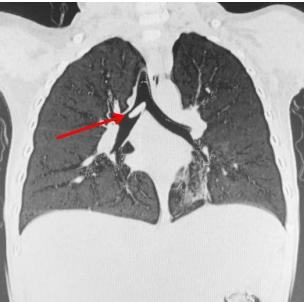

佛山市婦幼保健院在微信公眾號發文講述事件,指小周誤吞黃皮核後,家人初時覺得小周沒有甚麼異常,但後來小周日漸咳嗽、氣喘,多次看醫生都沒有明顯改善,直至去到佛山市婦幼保健院接受詳細檢查,才發現小周「氣管遠端-右主支氣管」有柱狀異物,並有「左肺肺炎」。

醫生分析,異物、即黃皮核落入氣管已有10天,不排除肉芽增生及黏膜炎症,加上黃皮核直徑大,極可能堵塞氣管開口,造成窒息、肺不張,甚至呼吸衰竭等危險,必須盡快做手術取出。

手術期間,醫生更發現,由於氣管環境溫暖、潮濕,黃皮核已經發芽、膨脹,大大增加取出難度。經過一場「拉鋸戰」,這顆發芽黃皮核終於從小周氣管內安全拔出。